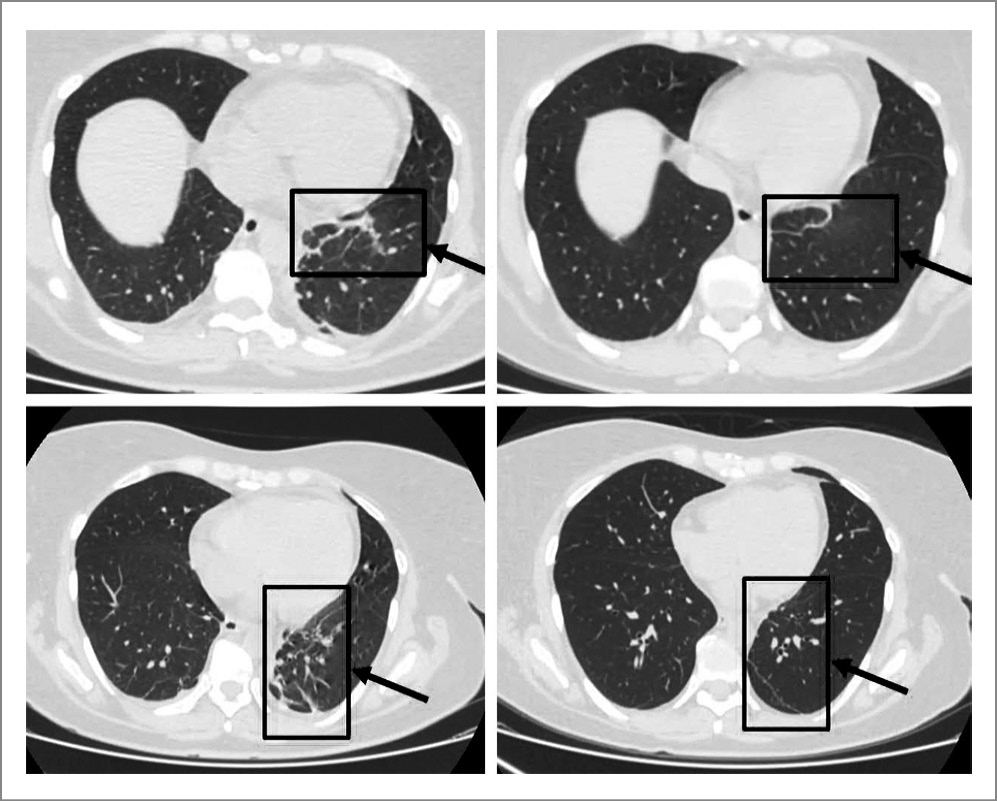

На следующий день после назначения дексаметазона в суточной дозировке 20 мг впервые за указанный период наблюдалось улучшение состояния пациентки в виде снижения температуры тела, уменьшения выраженности суставного синдрома. В последующем на фоне проводимого лечения также отмечалась положительная динамика по данным лабораторных и инструментальных исследований: СРБ – 19,8 мг/л; ферритин – 360 нг/мл; по КТ ОГК – разрешение двустороннего пневмонита, уменьшение внутригрудных лимфатических узлов (рис. 1).

Рис. 1. КТ-динамика изменений в легочной ткани на фоне терапии сГКС (слева – КТ ОГК от 30.10, справа – КТ ОГК от 05.11).